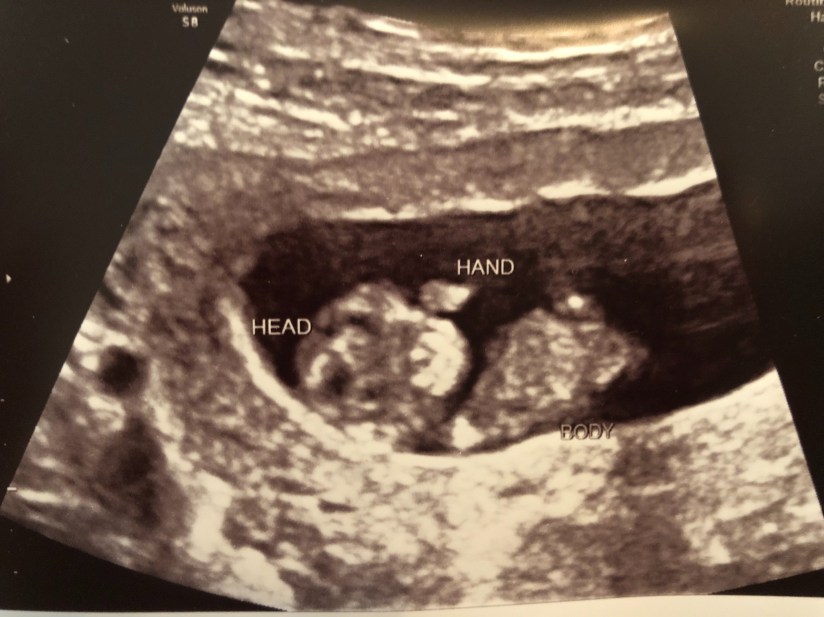

We did go back in pretty soon, in early September to have the screening done. (There is also a lot of debate with having this screening done… we did it with Annabelle Grace, but actually told our doctor NOT to tell us the results- I wanted them on record in case we lost her, I wanted to be able to look back and see if they had found anything. With this baby we chose to do it again, but DID want to know the results- not because we wouldn’t keep the baby, but so that we could prepare as best as possible if they did find anything we should know about. Plus, it’s an extra chance to see baby- who doesn’t want to see their baby any chance they’re given?!) We were told baby looked great, and of course got some new pictures! (We were a little over 13 weeks along at this point!)